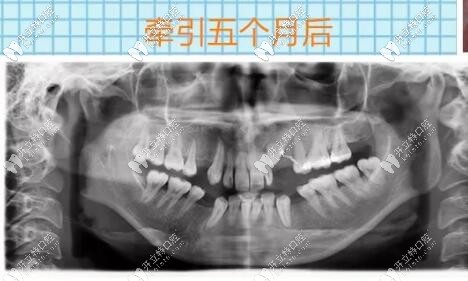

埋伏牙開(kāi)窗牽引5個(gè)月后

導(dǎo)萌手術(shù)結(jié)束之后的幾個(gè)月以后,逐漸迎來(lái)了曙光,看到了埋伏牙逐漸牽引出來(lái),那種激動(dòng)的心情無(wú)法言語(yǔ),時(shí)間過(guò)去太快了,到目前為止仍不后悔當(dāng)初的決定。